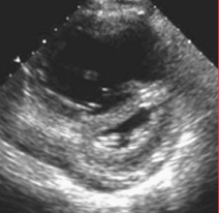

- Thickened RV free wall >5mm on the subcostal view (8; 9)

Thickened RV Wall